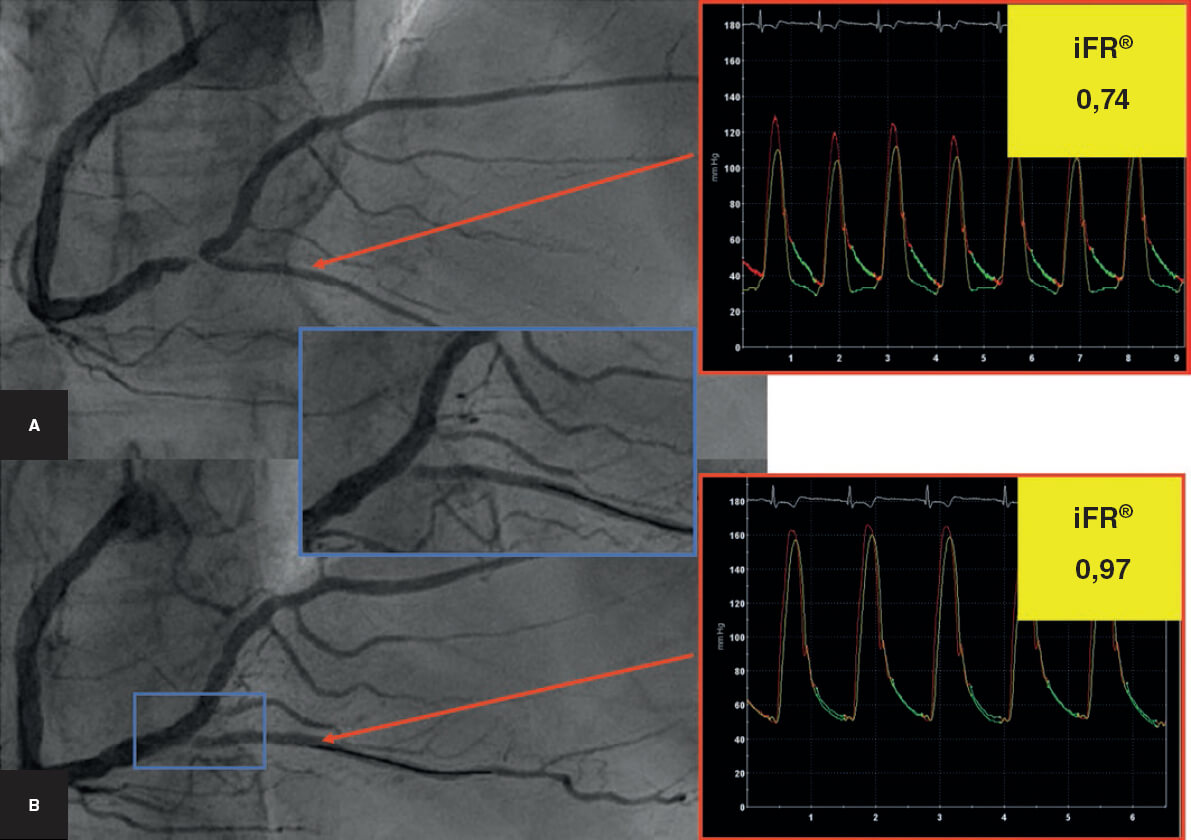

Estudio de la fisiología coronaria en las lesiones en bifurcación

Los índices de fisiología coronaria han demostrado una gran utilidad en la valoración de las lesiones angiográficamente intermedias. Específicamente, en las lesiones bifurcadas se han empleado para la valoración del resultado de la RL cuando se utiliza una técnica del stent provisional. En esta situación, la angiografía tiene muchas limitaciones para evaluar el resultado en un segmento que presenta una disección tras la dilatación con balón. Prueba de ello es la gran variabilidad de cruce a un segundo stent en las diferentes series de la literatura antes comentadas. La reserva de flujo fraccional se ha utilizado como fuente de información de interés frente a la angiografía. Así, aparentes malos resultados angiográficos presentan una reserva de flujo fraccional por encima del punto de corte para tratarlo50. La llegada de los nuevos índices de valoración fisiológica de las lesiones coronarias abre un nuevo campo en el estudio de las lesiones en bifurcación. El cociente diastólico instantáneo sin ondas (iFR), un índice fácil de obtener que no precisa inyección de adenosina, se muestra prometedor en la valoración del resultado de la RL durante la estrategia del stent provisional51 (figura 8).

Figura 8. Monitorización del resultado sobre la rama lateral (descendente posterior) con el cociente diastólico instantáneo sin onda (iFR). A: angiografía basal. B: tras el implante del stent en el vaso principal (coronaria derecha). Compromiso angiográfico del origen de la descendente posterior con un iFR > 0,90, por lo que no se precisa dilatación ulterior.